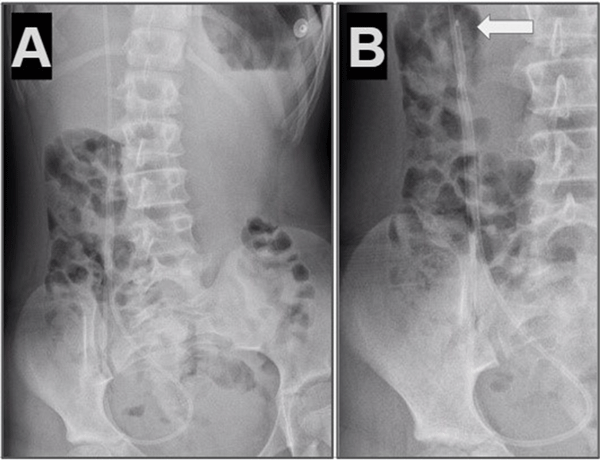

Caso 4. Paciente femenina de 10 años con antecedentes de nacimiento prematuro, hidrocefalia congénita y colocación DVP al mes de vida. Consultó por cuadro de cefalea y vómitos, tomografía de cerebro simple evidenció mayor tamaño ventricular en comparación con estudios previos. Radiografía de sistema mostró catéter distal fuera de la cavidad peritoneal (Figura 4).

Figura 4. Caso 4: A) Se observa Rx de tórax y abdomen (frente) con catéter distal a nivel abdominal con migración retrógrada. B) Magnificación de Rx de abdomen que evidencia catéter en doble caño con signo radiológico del “caño de escopeta” o “signo del anzuelo” (flecha blanca).